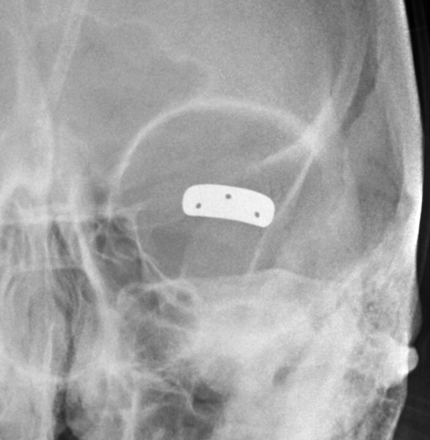

Implantation of gold and platinum eyelid weights into the upper eyelid is a static reanimation procedure for treating lagophthalmos.2 Although gold weights are more commonly used, platinum weights have a thinner profile and therefore offer an increased aesthetic benefit.3 Available eyelid implant designs include curved metal sheets with holes to permit anchoring with a suture (Fig 3) and flexible metal chains. In-growth of fibrous tissue through the holes also helps secure the weight in position. Eyelid weights are secured to the superficial aspect of the upper eyelid tarsal plate. The eyelid weights generally produce considerable streak artifacts on CT, which can obscure surrounding structures (Fig 4). Platinum and gold eyelid weights are considered MR imaging–compatible up to 7T4,5 but may cause local field inhomogeneity (Fig 5). Complications related to eyelid weight implantation include suboptimal eyelid contour, infection, allergic reaction, migration, and extrusion.6

Eyelid weight. Frontal radiograph shows a gold implant containing 3 drill holes at the level of the left upper eyelid.